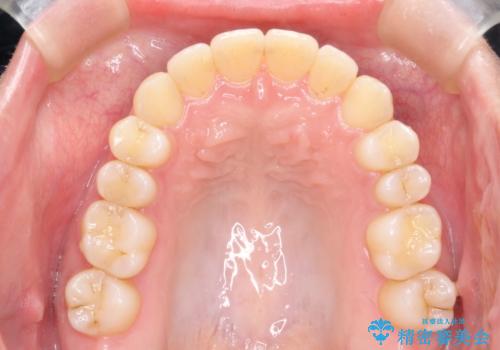

- 拡大・IPRによるスペースゲインを主とした非抜歯・マウスピース矯正を計画しました。

奥歯の位置関係の修正は難儀することが多いマウスピース矯正ですが、割とスムーズに奥歯の位置関係の修正をすることができました。

クロスバイトもきれいになり、きれいな歯並びとなりました。